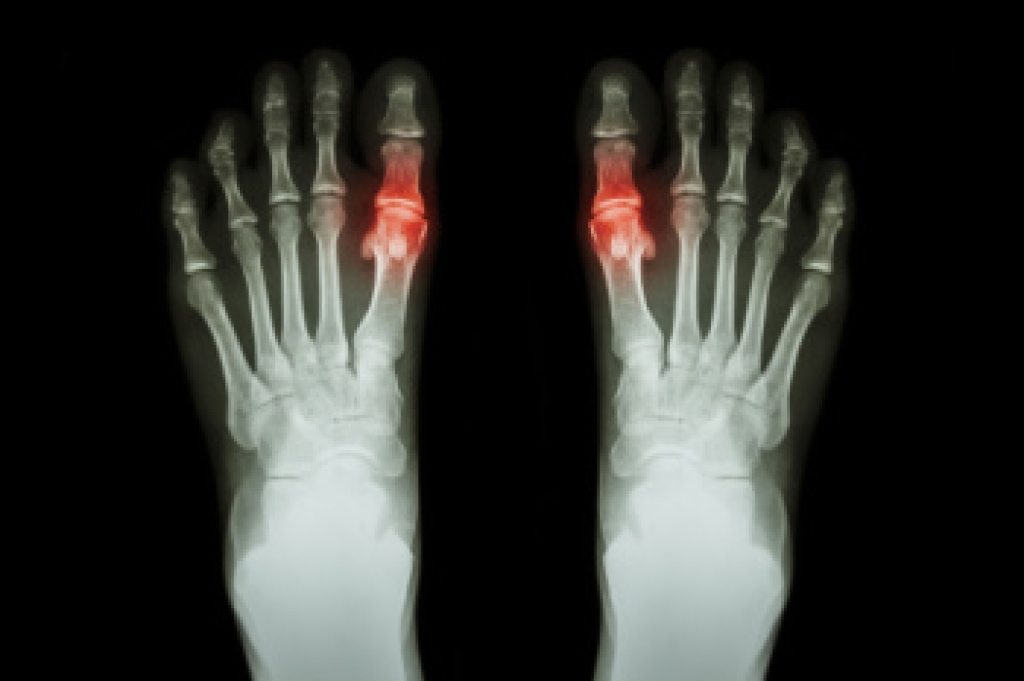

Gout, a form of arthritis caused by uric acid crystal deposits in joints, has several risk factors. Dietary choices high in purines, found in red meat, seafood, and alcohol, contribute to increased uric acid production. Obesity and certain medical conditions like hypertension and diabetes also raise the risk. Age and genetics play roles, with men over 40 and individuals with a family history being more susceptible. Prevention involves dietary adjustments, such as limiting purine-rich foods and alcohol consumption. Maintaining a healthy weight through a balanced diet and regular exercise reduces uric acid levels. Staying hydrated supports kidney function in removing uric acid from the body. Medications may be prescribed by a podiatrist to manage uric acid levels in high-risk individuals. If you have gout, it is strongly suggested that you are under the care of a podiatrist who can help you to manage this condition.

Gout is a form of arthritis that is characterized by sudden, severe attacks of pain, redness, and tenderness in the joints. The condition usually affects the joint at the base of the big toe. A gout attack can occur at any random time, such as the middle of the night while you are asleep.

- Intense Joint Pain - Usually around the large joint of your big toe, and it most severe within the first four to twelve hours

- Lingering Discomfort - Joint discomfort may last from a few days to a few weeks

- Inflammation and Redness -Affected joints may become swollen, tender, warm and red

- Limited Range of Motion - May experience a decrease in joint mobility